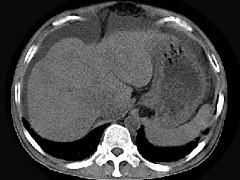

问题 男,44岁,有乙肝病史,现腹胀,右上腹痛,消化不良,消瘦、乏力、贫血、黄疸,血清转氨酶升高,白蛋白/球蛋白比值倒置。CT、MRI检查如下图,最准确的诊断是 ( )

选项 A.肝硬化并腹水 B.肝硬化并腹水、再生结节 C.肝硬化腹水、肝癌 D.肝硬化并再生结节 E.肝硬化并腹水、脂肪肝

答案 B